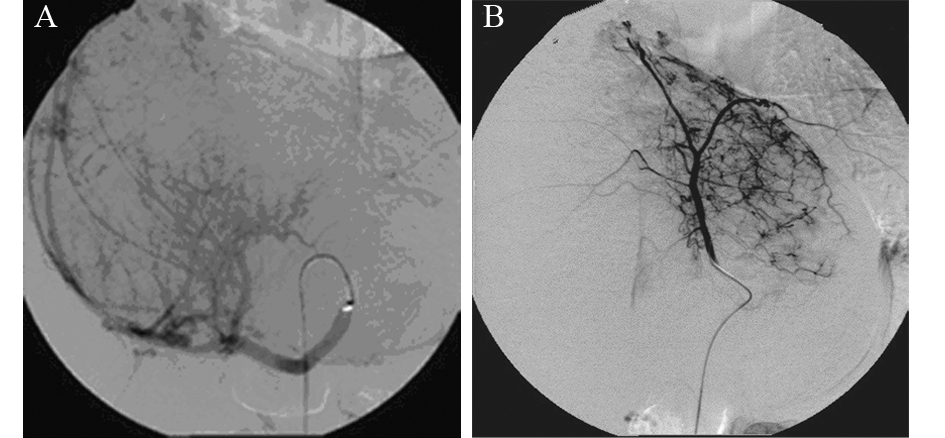

患者,女,31岁。于2013年3月4日查体发现肝脏肿物1月入院。无腹胀、腹痛、腹泻、发热等任何不适主诉。饮食正常,二便正常,体重无变化。查体:皮肤黏膜无黄染,无肝掌、蜘蛛痣。全身浅表淋巴结未触及。右肋部膨胀饱满,肝脏下缘位于右肋缘下约8 cm,剑突下5 cm,质地较软,边缘钝厚,表面无结节感,无压痛、触痛或叩痛。腹部移动性浊音(-);双下肢无水肿。辅助检查:上腹部CT示肝内巨大不均匀肿物,密度不均,内可见脂肪密度,不均匀强化,考虑肝脏巨大血管平滑肌脂肪瘤,见图 1。甲乙丙肝炎抗体均(-)。肝功能检查:正常;肿瘤标志物:AFP、CA199均在正常范围。2013年3月8日于我院行“剖腹探查术”:术中可见肝十二指肠韧带后方约20 cm×16 cm×16 cm巨大肿物,与肝门、肝左右叶、下腔静脉粘连,不能剥离,遂切除部分肿物送病理检查。术后病理结果:混合型脂肪肉瘤(上皮型与多形型之间过渡)。基于肿瘤巨大与周围组织粘连严重,无法手术切除,遂采取介入治疗,选择肝脏肿瘤供血动脉行灌注化疗及栓塞治疗。2013年4月9日第一次介入术中血管造影显示:肝动脉受压、移位、迂曲、增粗,实质期肝内可见巨块状肿瘤染色,由肝动脉及两侧膈动脉供血,肿瘤染色明显,肿瘤血管丰富交织呈网状,门静脉显影清晰,见图 2A、B。灌注化疗药物选择阿霉素、异环磷酰胺、达卡巴嗪;栓塞剂选择碘油、明胶海绵颗粒或海藻酸钠微球混合栓塞,术中患者均无不适。患者至2013年12月16日共行介入治疗6次,2014年1月20日复查CT示:肝脏肿瘤绝大部分液化、坏死,强化减轻,见图 3。血管造影示:肿瘤血管减少,血流量减少。随访:患者目前生存状态良好,无任何不适。

| With a large heterogeneous mass,uneven density,visible fat density,inhomogeneous enhancement 图1 肝脏原发性脂肪肉瘤患者上腹部CT Figure 1 The upper abdominal CT image of the patient with primary liver liposarcoma |